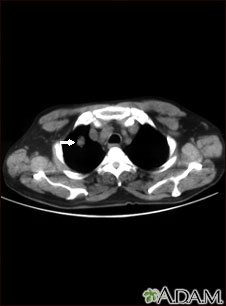

- Chest CT scan